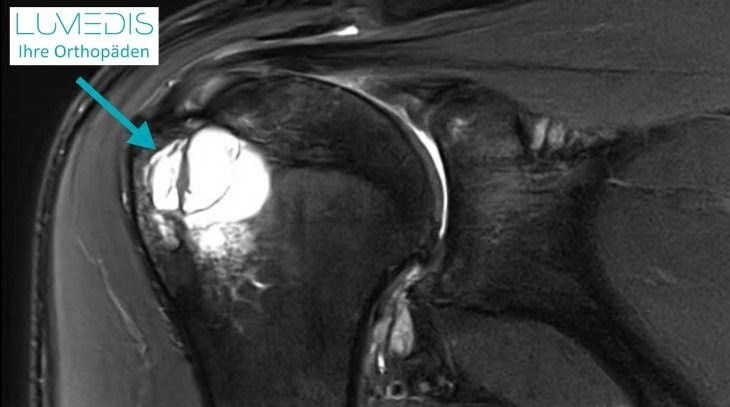

Abbildung einer aneurysmatische Knochenzyste

Der türkis Pfeil zeigt auf die Zyste im Oberarmkopf.

Im MRT stellt sich die aneurysmatische Zyste beispielsweise als scharf begrenzter, jedoch im Gegensatz zu den anderen Zystentypen gekammerter, blutgefüllter Hohlraum dar.